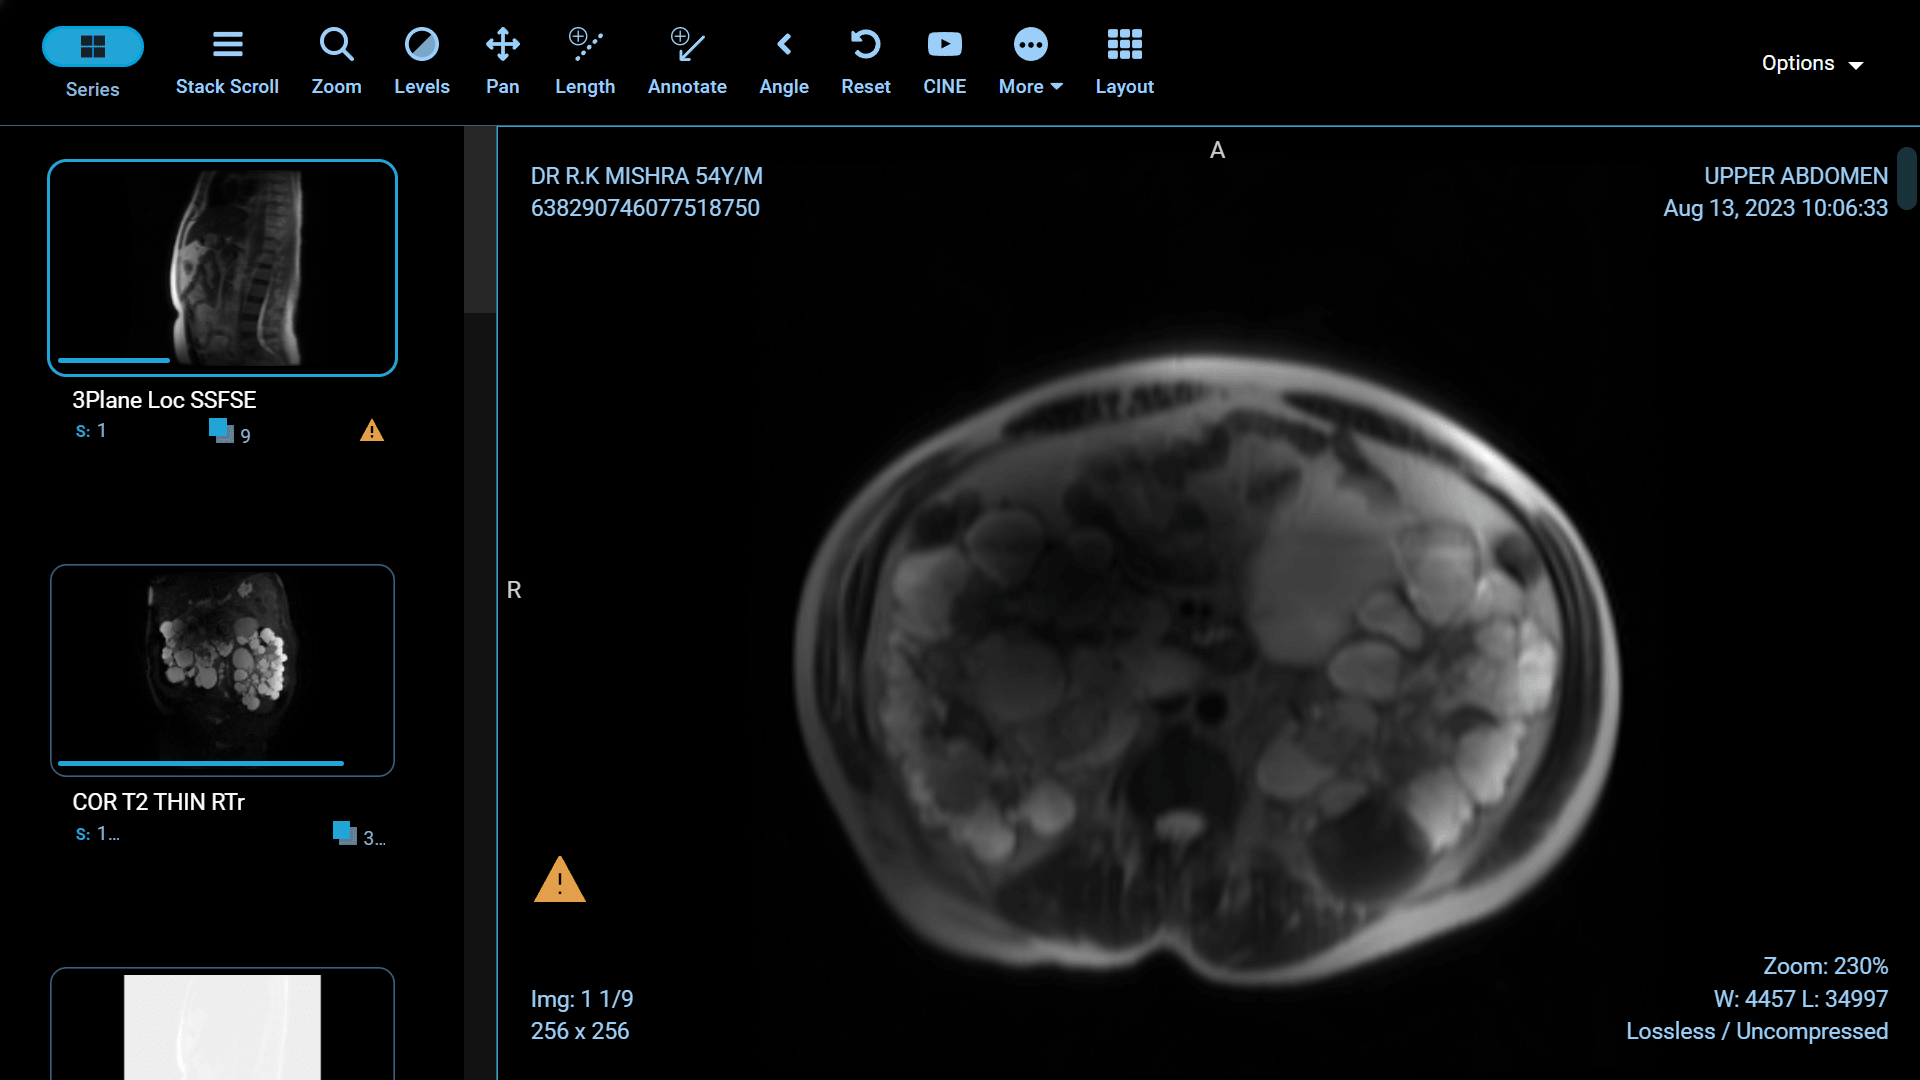

Polycystic Kidney Disease (PKD) is a genetic disorder characterized by the formation of fluid-filled cysts in the kidneys, which can lead to renal failure if left untreated. Fortunately, recent advancements in medical science have paved the way for more effective treatments and improved the quality of life for those affected by this condition. In this article, we will explore some of the groundbreaking innovations in PKD treatment.

Foam sclerotherapy is a medical procedure that involves injecting a specialized foam directly into kidney cysts. The foam is made by mixing a liquid sclerosing agent, typically a solution of alcohol or polidocanol, with air or gas to create a stable, persistent foam. This foam is then injected into the cyst through a thin needle under ultrasound or CT guidance.

The success of foam sclerotherapy lies in its ability to cause intentional injury to the cyst lining, promoting inflammation and scarring. This process leads to the collapse and sealing of the cyst, preventing further fluid accumulation and reducing the cyst's size.